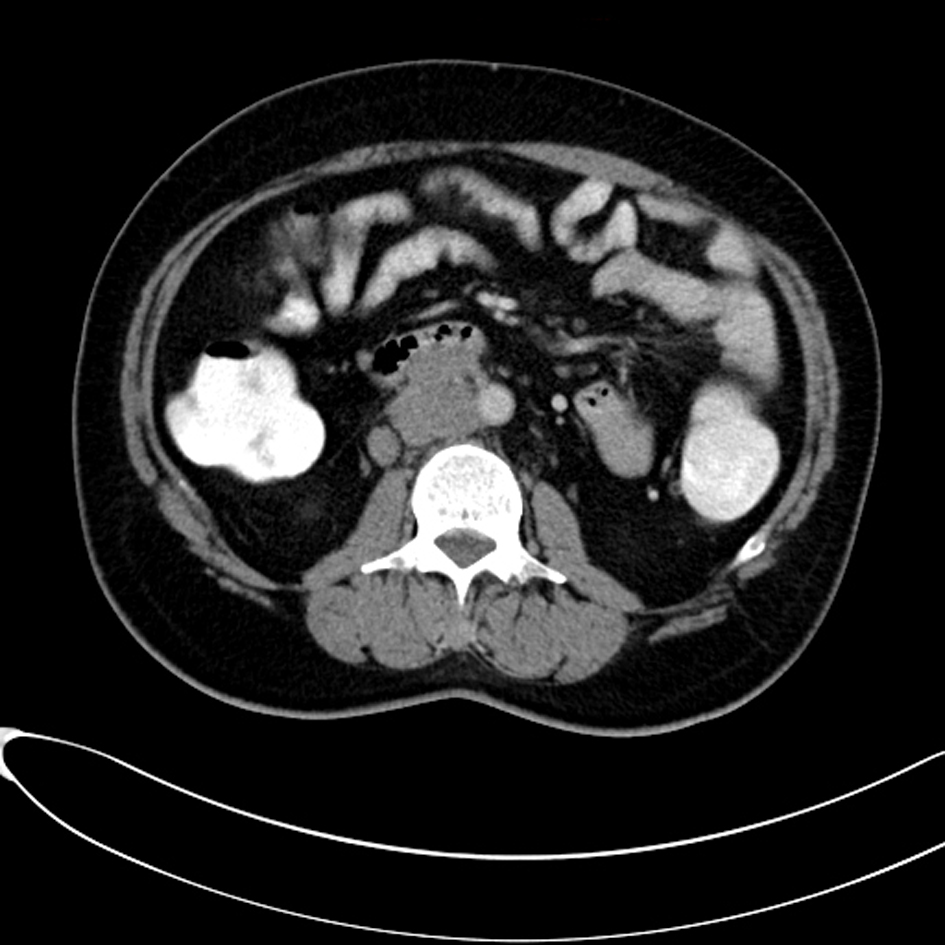

Computed tomography (CT) scan examination of the abdomen and pelvis was performed after administration of intravenous (IV) contrast material in portal venous phase which shows an empty scrotal sac with absence of the testicles and spermatic cord bilaterally (Fig. 1). A large homogenous mass is identified within the retro peritoneum of the right lower abdominal quadrant associated with small central area of low attenuation could represent an areas of cystic necrosis. No associated calcification is seen (Fig. 2). Small oval and homogenous structure is seen within the left aspect of the hemi pelvis just adjacent to the inguinal ring which represents a small atrophied left testicle with no masses (Fig. 3). There are multiple homogenous and matted lymph nodes metastasis located within the right Para-aortic region in close relation to the right renal hilum (Fig. 4).

![]() Click for large image | Figure 4. There are multiple homogenous and matted lymph nodes metastasis located within the right Para-aortic region in close relation to the right renal hilum. |

Approximately 75% of patients with seminoma present with disease limited to the testis, 20% have retroperitoneal adenopathy, and 5% have extra-nodal metastasis [3]. Check the retroperitoneal lymph node (especially at the level of renal hilum) in all cases of cryptorchidism complicated by malignancy like our case which presents by Para-aortic lymph nodes metastasis in close relation to the renal hilum. Absence of the spermatic cord is an important clue for cryptorchidism. Other differential diagnoses of retroperitoneal masses in adults include enlarged lymph nodes from lymphoma or infectious processes, neurogenic tumours, sarcoma and fibrosis.